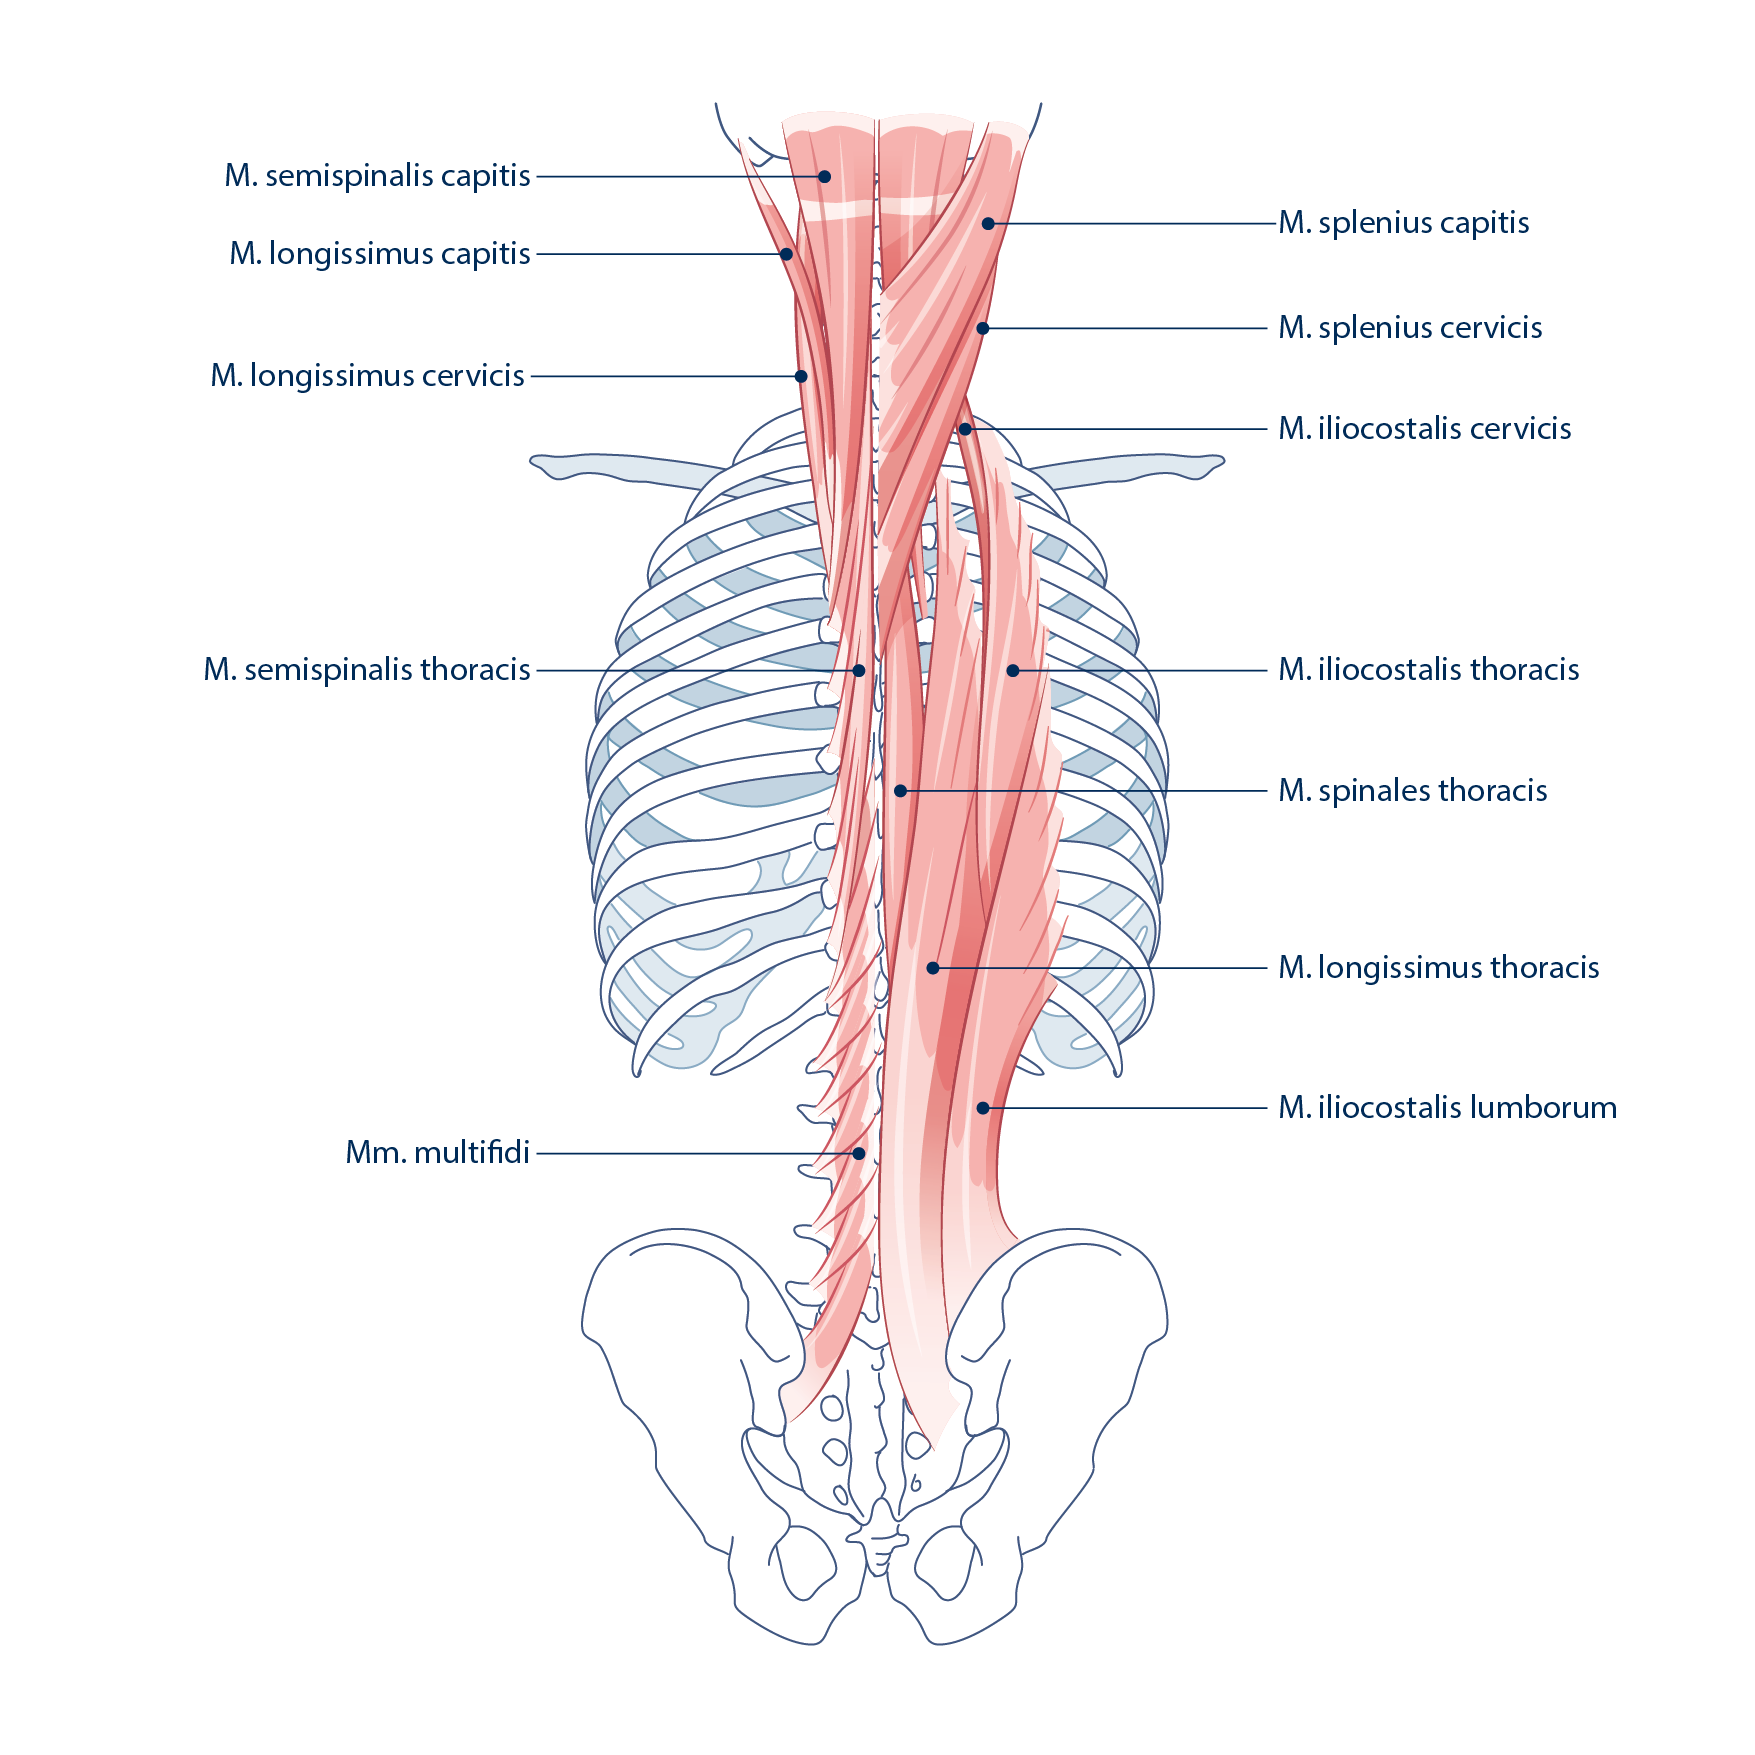

Weiterentwicklung der Technik – Vorteile des ultraschallgeführten Dry Needlings

Im traditionellen Dry Needling (ohne Ultraschallführung der Nadel) werden diverse Muskelgruppen aus Sicherheitsgründen nicht oder nur oberflächlich behandelt. Beispiele hierfür sind diverse Nacken-/Rückenmuskeln, welche in unmittelbarer Nähe zum Rückenmark oder zur Lunge stehen, wo heikle Strukturen verletzt werden könnten. Dazu gehört der Musculus erector spinae, also die der Wirbelsäule aufliegende Rückenmuskulatur.

Moderne Ultraschallgeräte machen es möglich, nicht nur die Zielmuskulatur und die Nadel, sondern auch Strukturen, welche zu verschonen sind (Lunge, Blutgefässe, Epiduralraum etc.) darzustellen. Dies erhöht die Sicherheit und Zielgenauigkeit der Behandlung und eröffnet die Möglichkeit, Muskeln und Triggerpunkte zu behandeln, welche bisher aus Sicherheitsgründen nicht in zufriedenstellender Qualität behandelt werden konnten. Dank entsprechender Infrastruktur und der Erfahrung können wir vielen Patienten zur ersehnten Schmerzlinderung verhelfen.